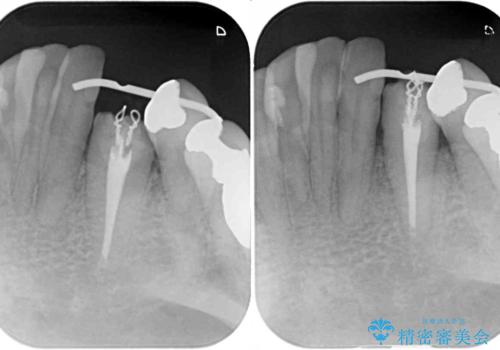

当該歯である犬歯は歯根が長く、安易に抜歯することはおすすめできないため、まずは部分矯正により歯根を引っ張り出し、その後歯周外科処置により歯槽骨や歯肉の状態を整え、最終的にはオールセラミッククラウンにて補綴治療を行うこととしました。

矯正治療中は汚れが溜まりやすく、歯肉からの出血が続きましたが、最終的には歯を保存して安定した状態で補綴治療を行うことができました。